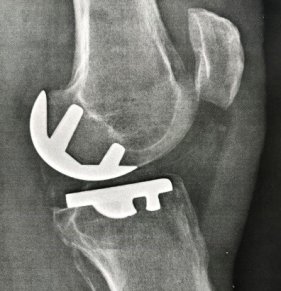

La prothèse unicompartimentale de genou

Qu'est-ce que la prothèse unicompartimentale de genou ?

La prothèse unicompartimentale remplace le condyle fémoral et le plateau tibial d'un seul compartiment. Il s’agit le plus souvent d’une arthrose du compartiment fémoro-tibial interne, qui sera prise en exemple.

Pour qui ?

Pour des patients ayant une arthrose isolée du compartiment fémoro-tibial interne, avec un genou stable (ligaments en bon état), sans grande déformation axiale, avec un indice de masse corporel dans les normes. Ces conditions restrictives doivent être réunies pour garantir un bon résultat dans le temps.